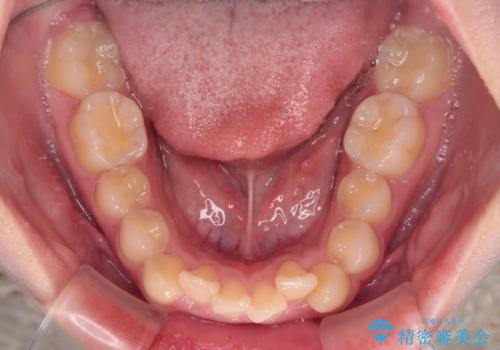

- デコボコになっている前歯を気にして来院された患者様です。

口元の突出感は気になっていないものの、デコボコを解消すると口元が前方に突出する可能性があるため、上下左右の第一小臼歯4本を抜歯して、ワイヤー装置にて矯正治療を行うこととしました。

下の前歯が隠れてしまうほど深く咬みこんでいたため、上顎前歯が前方に突出しているような印象がありましたが、咬み合わせが改善され、整った口元に仕上げることができました。